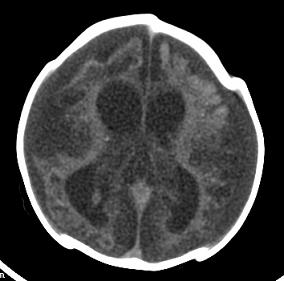

男,4个月大,2个月前无诱因下四肢抽搐、伴呕吐,近2天来抽搐频发,伴发热。查体:双眼疑视,神萎、纳差;颈抵抗,四肢张力高。

病史太长了,原因不好定,不过如果2个月前小儿正常的话可考虑积水型无脑畸形,积水型无脑畸形小儿刚生下来表现可正常,存活一两个月后出现症状.

另不除外缺血缺氧性脑病,感染等改变

2个月前缺血缺氧性脑病留下的后遗症。

脑出血后,软化灶形成了。脑发育不良

支持缺血缺氧性脑病留下的后遗改变(脑软化灶+脑发育不全+双侧慢性硬膜下积液+小头畸形)。

要注意化脓性脑膜、脑炎,硬膜下积脓,脑积水的可能,建议腰穿助诊。